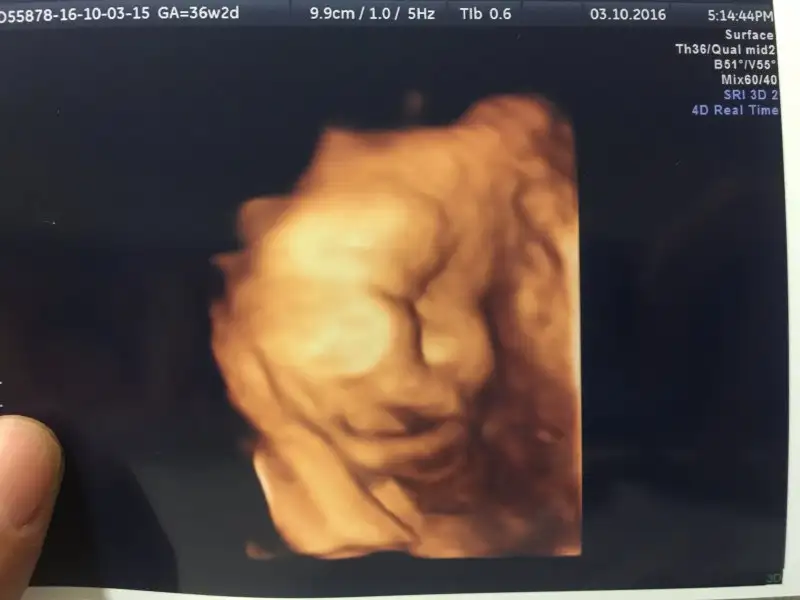

Kucagina almana az kaldi nasipse.saglikla kucagina aldigin gunleri gorursun insallah.Kızlar bizimde bu aksam randevumuz vardı 36 + 2 yiz günümüze uygun gidiyoruz. Kasılmalar ve sancılar başlamış ufak ufak. Ateş kafa aşagıda duruyo. Dogum kanalına yaklaşmış ama henüz girmemiş. Haftaya tekrar kontrolümüz var. Bu kasılmalar devam ederse muayene ederim haftaya açılma için dedibuda oğluşun profil fotosu :) selamı var teyzoşlarına ..

Oy masallah Ates Bey'e :) benimde yarin kontrolum gecen yuzunu gostermedi insallah bu sefer gosterir :)Kızlar bizimde bu aksam randevumuz vardı 36 + 2 yiz günümüze uygun gidiyoruz. Kasılmalar ve sancılar başlamış ufak ufak. Ateş kafa aşagıda duruyo. Dogum kanalına yaklaşmış ama henüz girmemiş. Haftaya tekrar kontrolümüz var. Bu kasılmalar devam ederse muayene ederim haftaya açılma için dedibuda oğluşun profil fotosu :) selamı var teyzoşlarına ..

Oyy kurban olsunlar kuzusuna ağzını yesinler bunun ateş paşaya maşallahKızlar bizimde bu aksam randevumuz vardı 36 + 2 yiz günümüze uygun gidiyoruz. Kasılmalar ve sancılar başlamış ufak ufak. Ateş kafa aşagıda duruyo. Dogum kanalına yaklaşmış ama henüz girmemiş. Haftaya tekrar kontrolümüz var. Bu kasılmalar devam ederse muayene ederim haftaya açılma için dedibuda oğluşun profil fotosu :) selamı var teyzoşlarına ..

Kızlar bizimde bu aksam randevumuz vardı 36 + 2 yiz günümüze uygun gidiyoruz. Kasılmalar ve sancılar başlamış ufak ufak. Ateş kafa aşagıda duruyo. Dogum kanalına yaklaşmış ama henüz girmemiş. Haftaya tekrar kontrolümüz var. Bu kasılmalar devam ederse muayene ederim haftaya açılma için dedibuda oğluşun profil fotosu :) selamı var teyzoşlarına ..